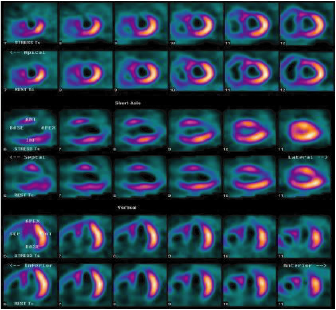

Los estudios de medicina nuclear en cardiología o cardiología nuclear son auxiliares diagnósticos que utilizan diversos radiotrazadores de baja energía que al ser inyectados por la vena al paciente, emiten rayos gama que son captados por un tomógrafo especial (SPECT cardiaco).

Estos radiotrazadores demuestran cuanta sangre llega al músculo cardiaco a través de las arterias coronarias, a esto se le

conoce como evaluación de la perfusión miocárdica. Cuando existe la sospecha de angina de pecho y/o infarto (cardiopatía isquémica) este estudio puede demostrar la disminución de sangre en el musculo cardiaco y su repercusión en la función del corazón.

La evaluación de la perfusión miocárdica con SPECT cardiaco se realiza mediante dos imágenes de 20 minutos, la primera imagen se obtiene una hora después de la inyección del radiotrazador en reposo y la segunda imagen se obtiene después de la inyección del radiotrazador mientras que el paciente hace una prueba de esfuerzo en banda sin fin o bien, para las personas que no pueden hacer ejercicio físico, con la administración de un medicamento. Todo el proceso tiene una duración de 3 a 4 horas y esta supervisado por especialistas en cardiología nuclear.

Existen otras indicaciones de los estudios de cardiología nuclear como por ejemplo la evaluación de la función cardiaca y de las enfermedades infecciosas o inflamatorias del corazón.